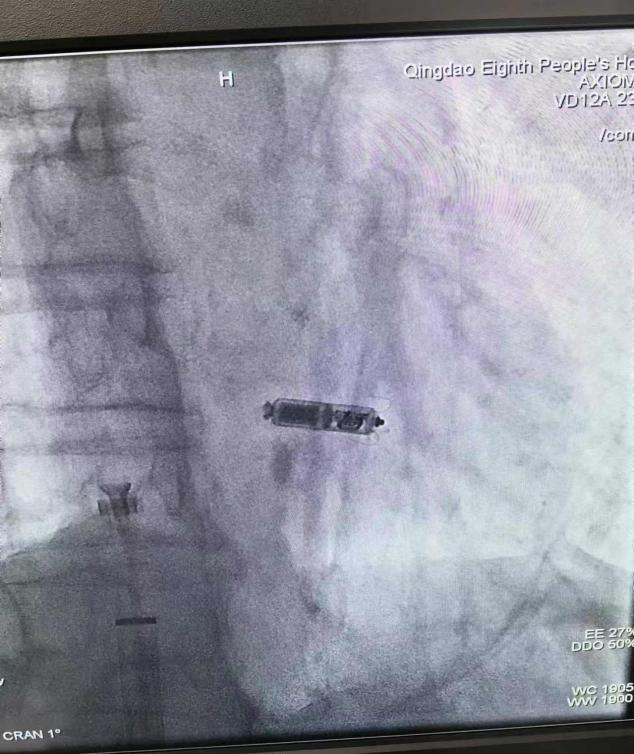

手术如期顺利开展,手术团队仅用半个小时就成功为患者植入无导线起搏器,术后起搏器感知功能开启,实现心室跟踪心房起搏,心室率恢复至每分钟70次左右,患者生命体征平稳,康复前景乐观。

无导线起搏器植入术是一种新兴的心脏电生理干预技术,旨在通过微创手术方式植入胶囊大小的起搏器,以治疗缓慢性心律失常。与传统的起搏器相比,无导线起搏器植入术无须经静脉植入电极导线和制作囊袋,避免了电极导线脱位、磨损、囊袋及起搏系统感染等相关并发症;其体积小且轻,直接放置于心腔,患者日常生活中基本感受不到起搏器的存在,大大提高了患者的生活质量;该起搏器使用寿命最大可达20年,还可以进行1.5 T/3.0 T全身核磁共振扫描检查。